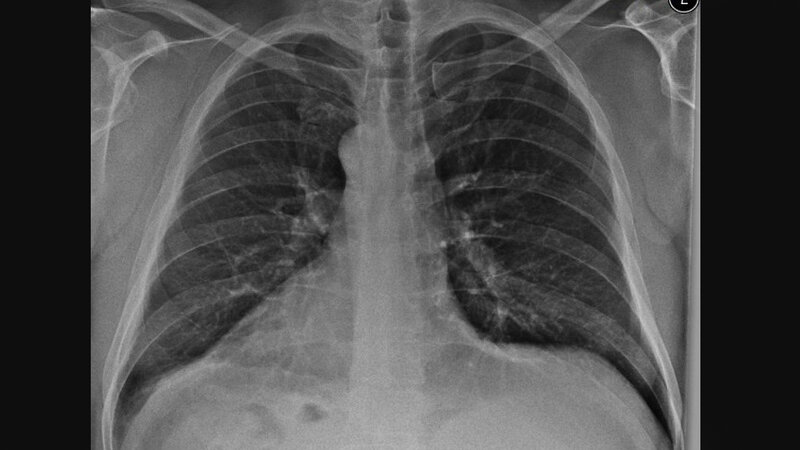

Die Dextrokardie beschreibt ein nach rechts in der Achse gerichtetes Herz. Sie ist vorrangig das Ergebnis einer varianten Entwicklung. Die Dextrokardie kann bei verschiedenen anderen klinischen Veränderungen und im unterschiedlichen Alter der Patienten entdeckt werden.

Dextrocardia is defined as a right-sided heart with a base-apex axis directed rightward. It is resulting from a variation in cardiac development. Dextrocardia can be discovered in various clinical settings and at various patient ages.